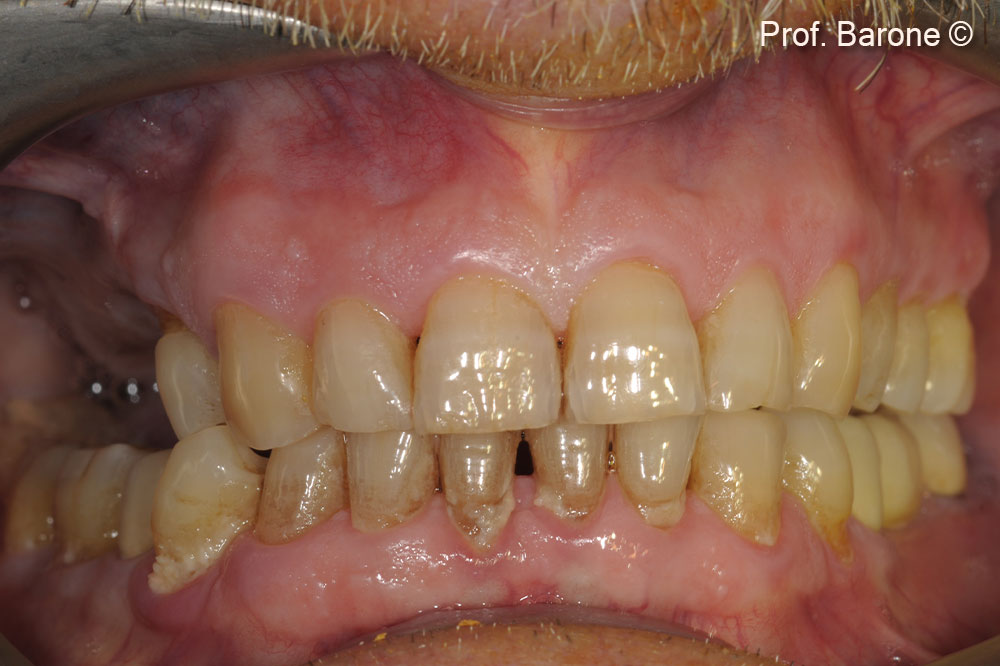

In a male patient (71 years old), the residual ridge height doesn’t allow implant placement.

Partial edentulism first quadrant